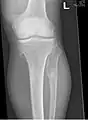

múltiples osteocondromas alrededor de la rodilla

El diagnóstico de HMO se basa en establecer una correlación precisa entre las características clínicas mencionadas anteriormente y las características radiográficas características. Los antecedentes familiares pueden proporcionar una pista importante para el diagnóstico. Esto se complementa con pruebas de los dos genes en los que se sabe que las variantes patogénicas causan HMO, a saber, EXT1 y EXT2. Una combinación de análisis de secuencia y análisis de deleción de todas las regiones codificantes de EXT1 y EXT2 detecta variantes patogénicas en 70 a 95% de los individuos afectados.[3][4] El sello distintivo del diagnóstico radiográfico es la presencia de osteocondromas en los extremos metafisarios de los huesos largos en los que la corteza y la médula del osteocondroma representan una extensión continua del hueso huésped. Esto es fácilmente demostrable en radiografías de rodillas.[1]